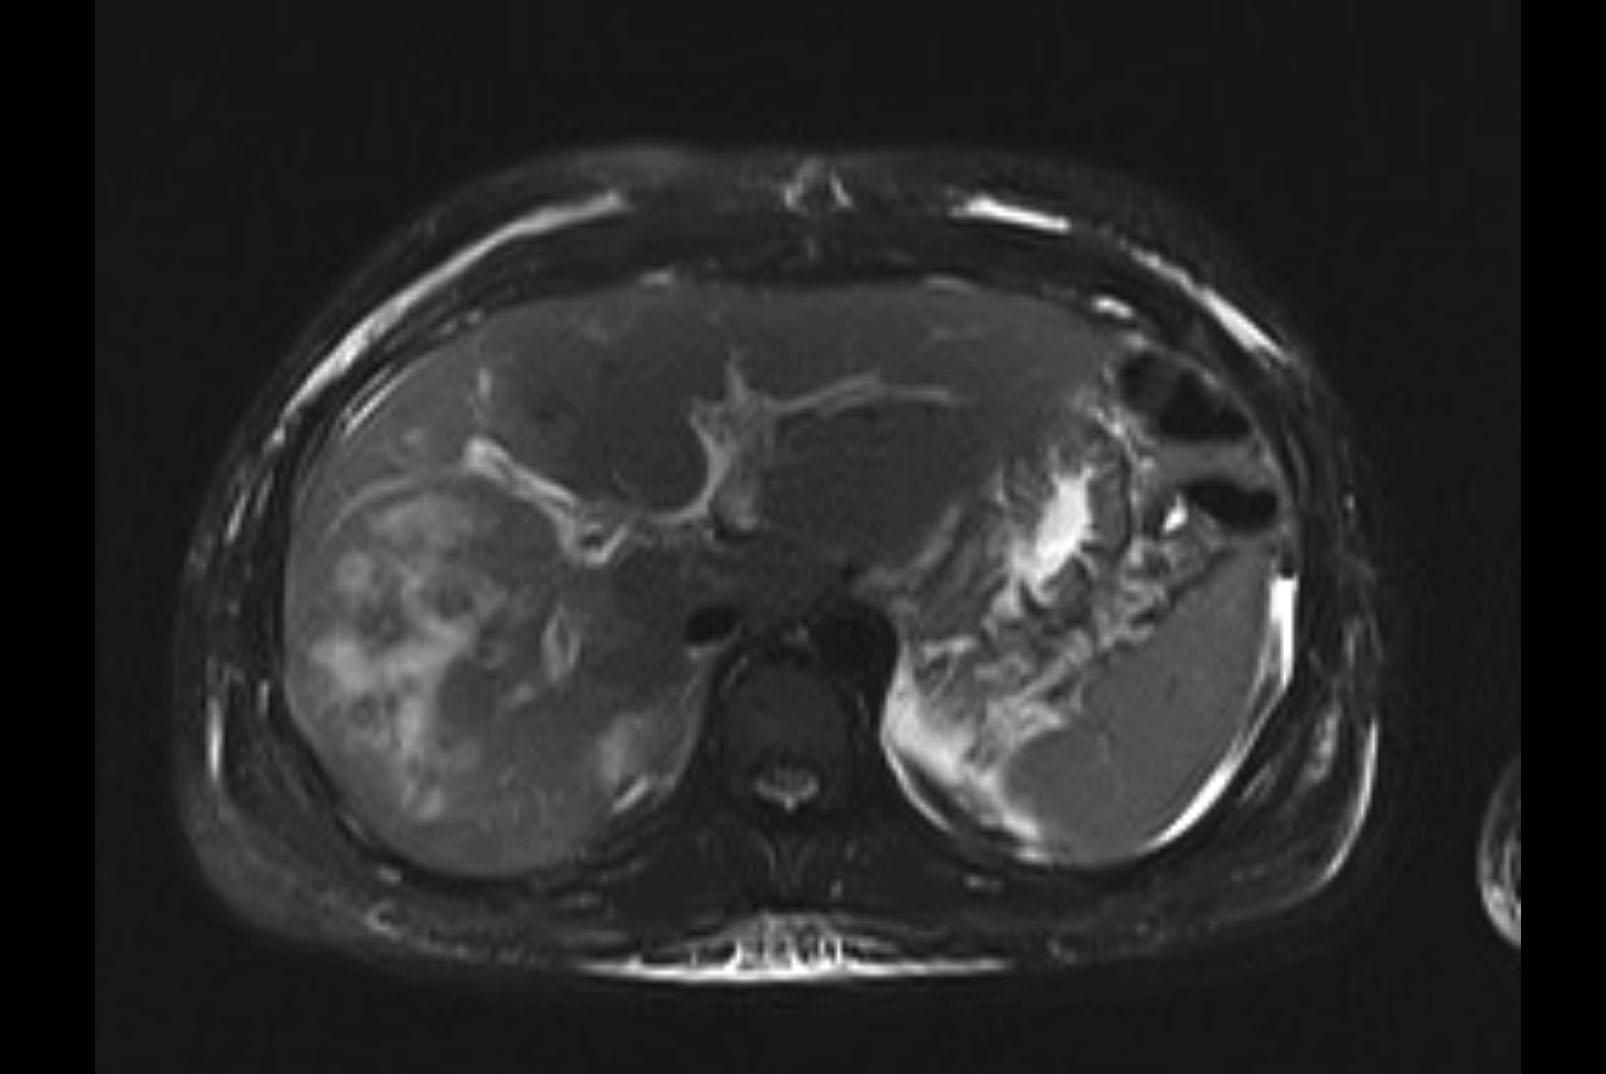

MRI T2